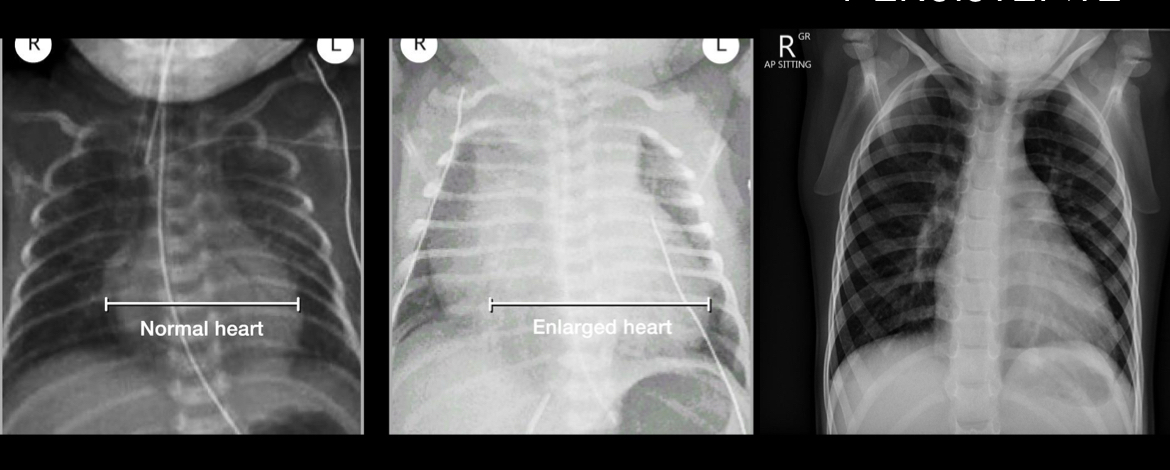

cortocircuito pequeño:normal

Cardiomegalia

Dilatacion arteria pulmonar

Incremento vasculatura pulmonar parahiliar

Cardiomegalia en caso cronico. En niños mas de 0.6